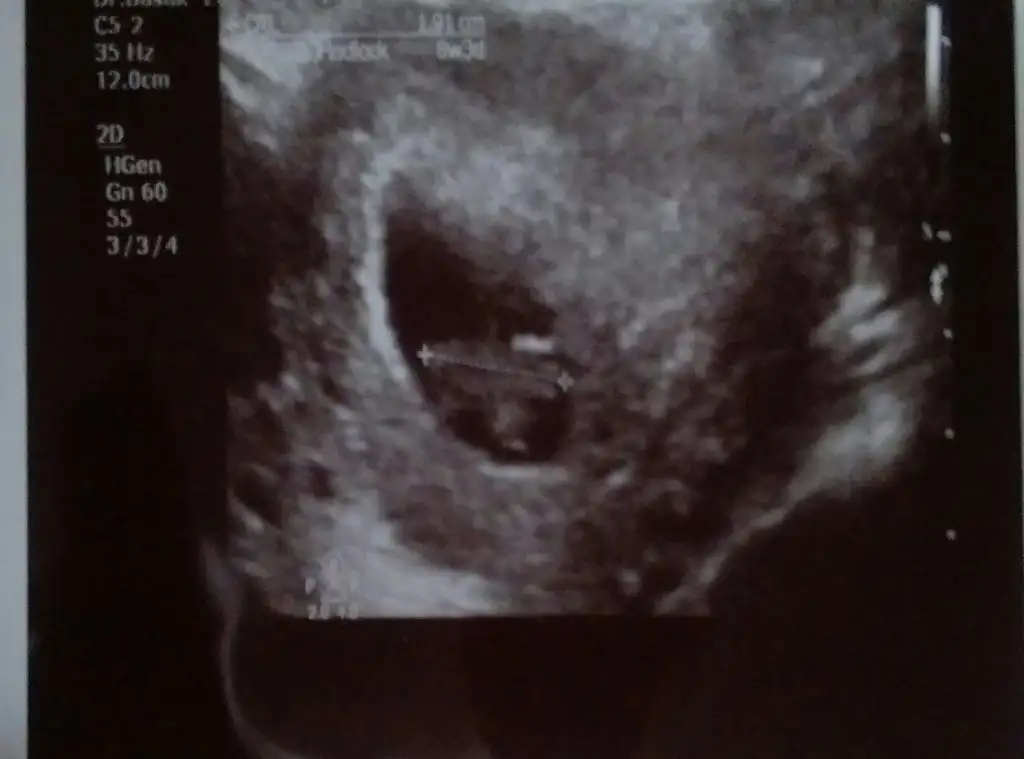

herkese merhaba kızlar :KK66: evet miniğimizi bizde gördük geldik ilk kez kalbini dinledik..:anneadayı:.9 haftam bitiyor zatıallleri 8+3 e uyumlu çıktı ...özele gittim bugün hiç baktırmamışım gibi testleri yeniden verdim idrarda dahil...iyotlu folik asit kullanmamı söyledi 3 4 tane isim yazdı...buda resmimiz :emir_bebek:

• IMAG1382_1.webp

16,9 KB · Görüntüleme: 95